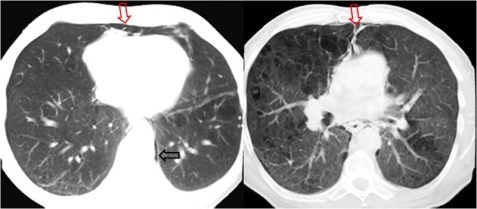

Este signo fue inicialmente descrito en la radiografía de tórax como la presencia de aire entre la pleura parietal y el diafragma. Pero es más fácil de reconocer en la TC, como en el caso que presentamos: las imágenes muestran una colección de aire extrapleural en el espacio retroesternal (flechas rojas), limitada por la pleura parietal.

Así mismo hay una pequeña cantidad de neumomediastino paravertebtal (flecha negra).